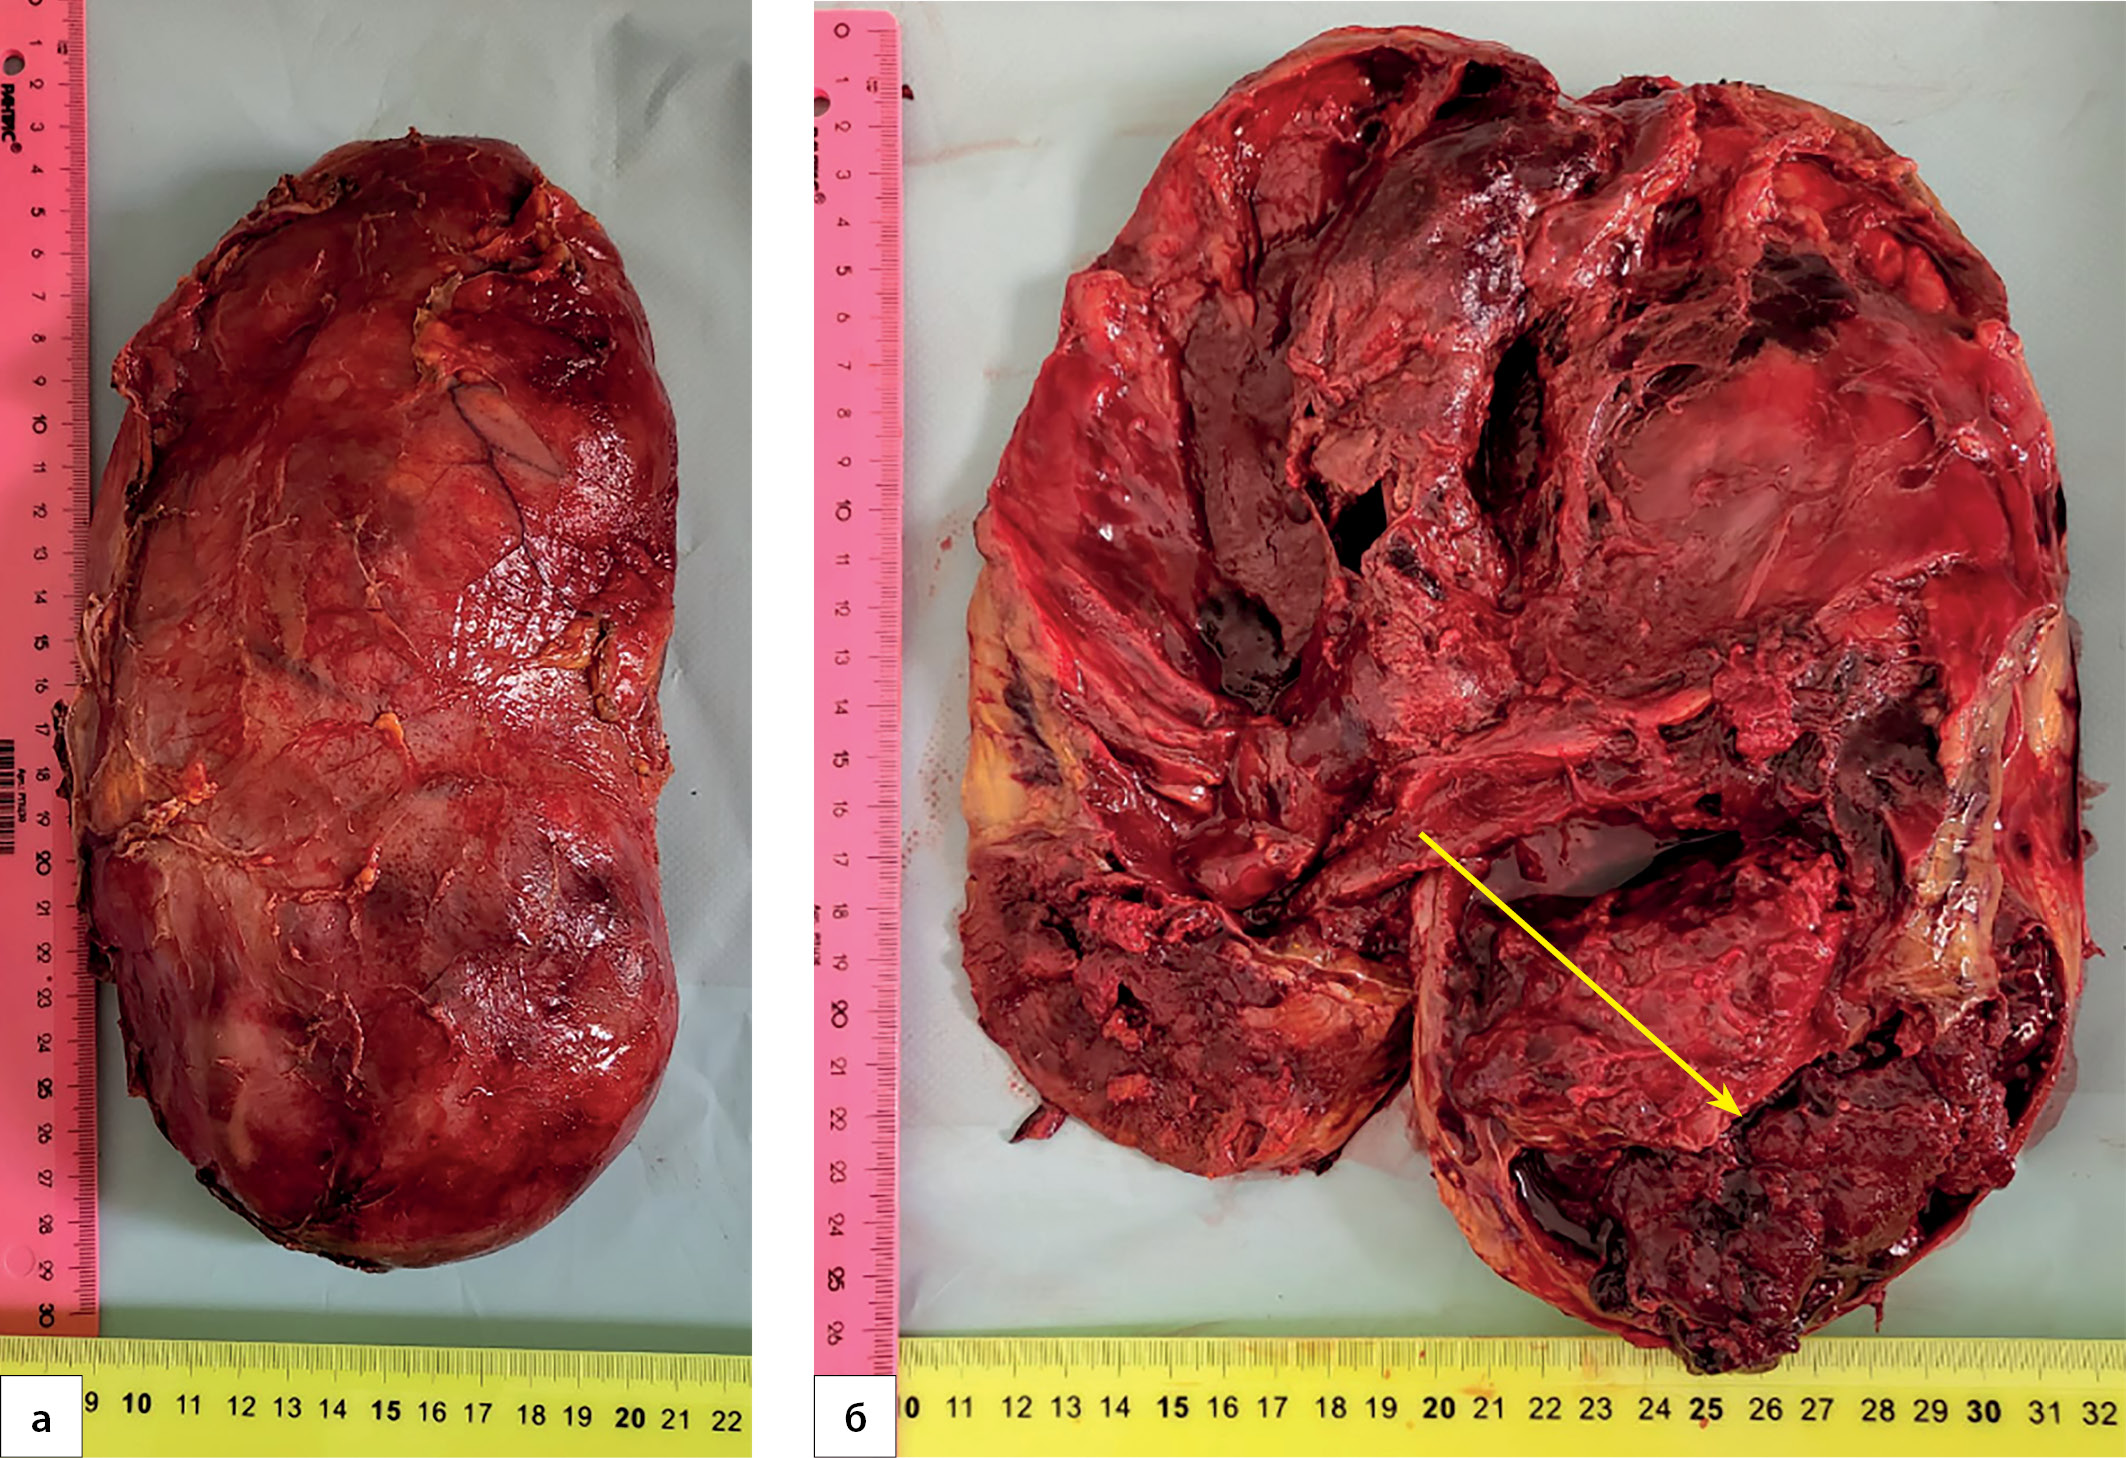

3. Рисунок 3. Пациентка П., 38 лет. Макропрепарат опухоли надпочечника: а) общий вид; б) на разрезе видны некротические изменения, разрыв капсулы, гематома (маркирована стрелкой). | |